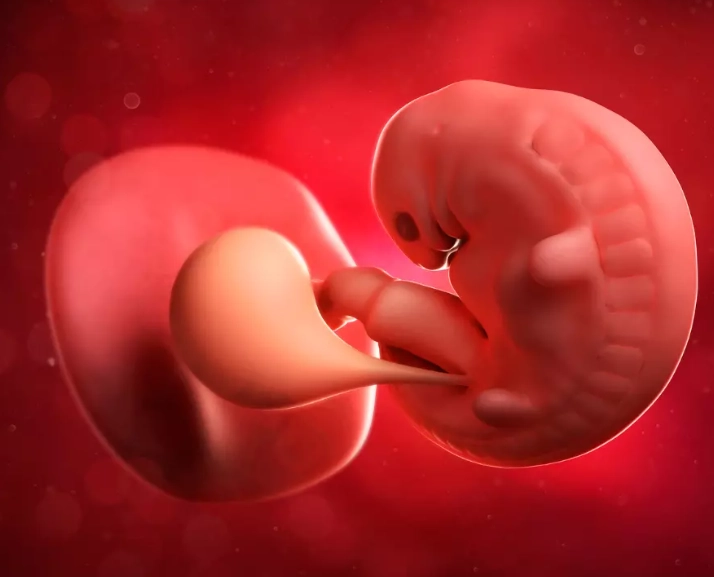

At 5 weeks, an ultrasound (usually transvaginal for clarity) might seem early, but it can show important structures:

- Gestational Sac: A small, black, fluid-filled circle within the uterus. This confirms the pregnancy is intrauterine (not ectopic).

- Yolk Sac: Often visible by the end of the 5th week. It nourishes the embryo before the placenta takes over. Seeing it is a very good sign.

- Fetal Pole: The first visual evidence of the developing embryo. It may be visible as a tiny thickening on the edge of the yolk sac.

Don't panic if you don't see a heartbeat yet. It typically becomes visible around 6 weeks. The absence of a heartbeat at 5 weeks is not a sign of an unhealthy pregnancy.